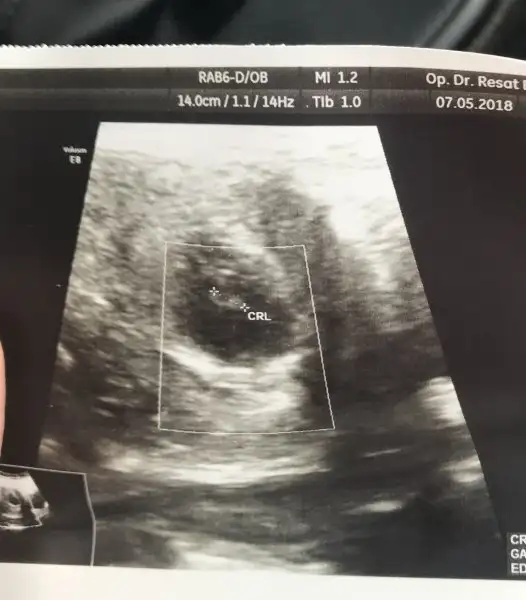

Kızlar bu arkadaşımın bebisi lütfen yorum yapar misiniz

Kızlar tahminlerinizi bekliyorum 7+5

• 20180704_120828_Burst01-1.webp

21,4 KB · Görüntüleme: 222